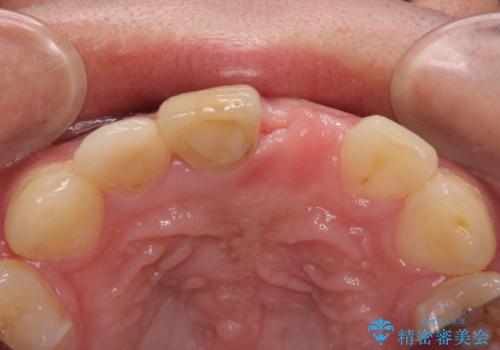

- 転倒により前歯を失ったところにインプラント治療を受けたいとのことで来院された患者様です。

転倒を機に矯正治療を行ったようで、歯列が整い、インプラントのスペースができたとのことで受診をされました。

骨量は十分にあったため、インプラント埋入後速やかに仮歯を装着して、歯肉治癒後にオールセラミッククラウンによる補綴治療を行うこととしました。